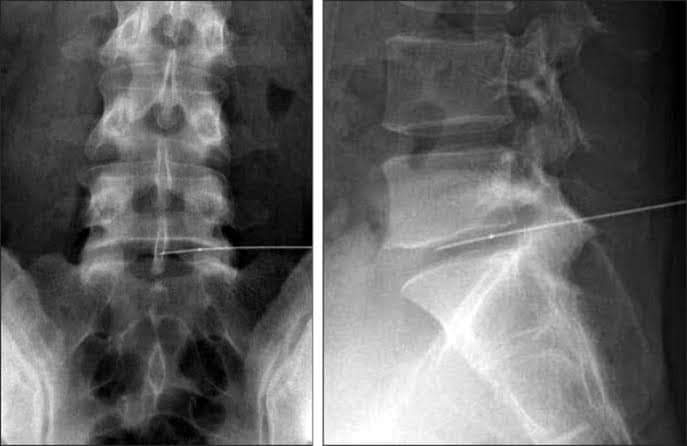

لأول مرة فى مستشفيات دمياط اجراء عمليتي كى لفقرات المفاصل الفقرية بالعمود الفقرى وكى نواة الغضروفو تردد حرارى وكى للعصب الخامس تحت التصوير الفلورسكوبى بمستشفى دمياط العام

تم اجراء عملية تردد حرارى كى لفقرات للمفاصل الفقرية العمود الفقرى وكى نواة الغضروف بالتردد الحرارى للغضروف القطنى تحت التصوير الفلورسكوبى و ذلك للمرة الاولى بمحافظة دمياط بمستشفى دمياط العام

لسيدة تعانى من الام والتهاب بمفاصل فقرات العمود الفقرى بعد اجراء التحاليل والفحوصات والاشعات اللازمة للحالة كما تتم متابعة الحالة بالمستشفى كما تم إجراء عملية تردد حرارى وكى للعصب الخامس تحت التصوير الفلورسكوبى و ذلك للمرة الاولى في محافظة دمياط أيضا

لسيدة تعانى من ألآم والتهاب بالعصب الخامس وذلك بعد اجراء التحاليل والفحوصات والاشعات اللازمة للحالة بمعاونة طاقم من الجراحين و التمريض و الفنيين العاملين بالمستشفى